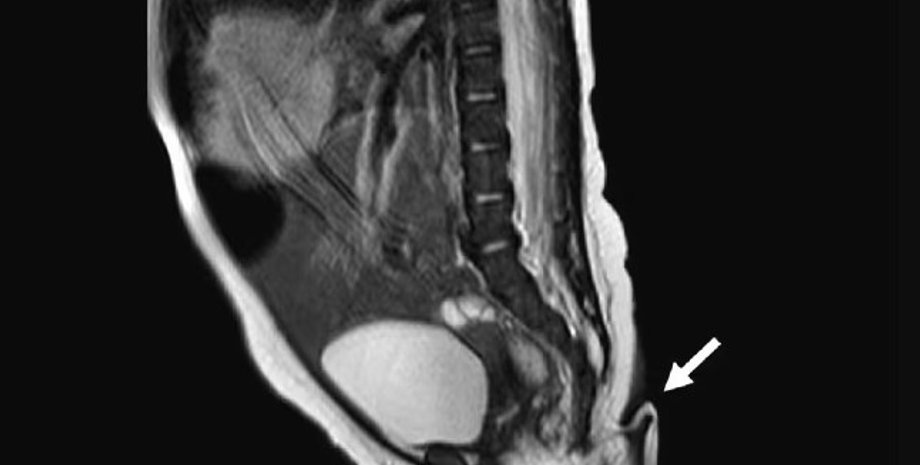

Медики на чолі з доктором Хосуе Руеда вважають, що дитина стала першою дитиною, що народилася з хвостом, у Мексиці. Крихітка з'явилася на світ у лікарні в Нуево-Леоні в результаті кесаревого розтину. Батьки дівчинки були здорові, проте медики швидко помітили 5,7-сантиметровий хвіст, який був м'яким із загостреним кінчиком, покритим шкірою та тонкими волосками.

Співробітники лікарні провели додаткове сканування та виявили, що наріст не є наслідком спинальної дизрафії — проблема з хребтом, за якої він не формується належно і може призвести до появи хвостового наросту в нижній частині хребта.

Медики зазначають, що в діаметрі "хвіст" був лише від 3 до 5 мм, був покритий шкірою та тонкими волосками. Цікаво, що лікарі могли пасивно рухати "хвіст", не викликаючи у дівчинки болю, проте мимовільних рухів відростка не спостерігалося. Крім того, медики провели тест на реакцію, "вколовши" відросток голкою, в цей момент новонароджена заплакала.

Дослідники продовжили вивчати "хвіст". Аналіз показав, що він складається з м'яких тканин, артерій, вен та пучків нервів. Загалом у світі зареєстровано лише 195 випадків людських "справжніх хвостів" (до 2017 року).